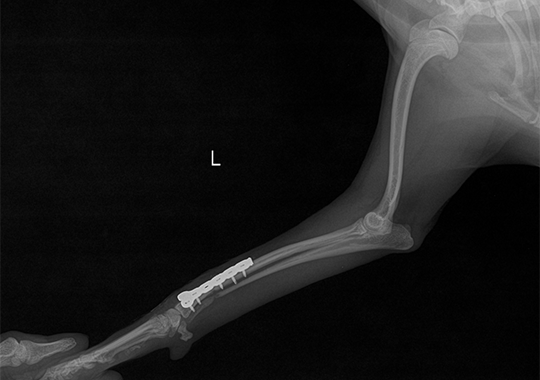

요골 골절 수술 전

요골 골절 수술 후

정형외과 케이스

본원은 실력 있는 전문 의료진과 최첨단 시설로 정형외과에서 좋은 예후들을 보여드리고 있습니다. 강아지에게서 쉽게 발생하는 슬개골 탈구, 십자인대 단열 뿐 아니라 다양한 고난도 케이스를 다루고 있으며, 특히 골절 수술은 회복률이 높고 타원 수술 후, 유합부전으로 본원에 내원하여 재수술에 성공한 사례가 많습니다.